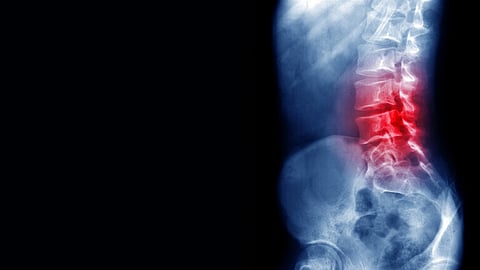

كشفت صور مروعة بالأشعة السينية تفاصيل إلحاق الغاز الضاحك الضرر بالعمود الفقري لرجُل، الأمر الذي حرمه من القدرة على المشي.

وكشف فحص التصوير بالرنين المغناطيسي أن الحبل الشوكي بدأت تظهر عليه علامات حالة عصبية تعرف باسم اعتلال النخاع، والذي يحدث أحيانًا بسبب نقص فيتامين B12، ويحدث هذا عندما يتم ضغط الحبل الشوكي بسبب الالتهاب في المناطق المحيطة.

ووجد الأطباء أن جزءًا من النخاع الشوكي، والعمود الظهري، المسؤول عن الشعور باللمس، قد أصيب بجروح بالغة، وكشفت الفحوصات عن وجود آفة متطورة.